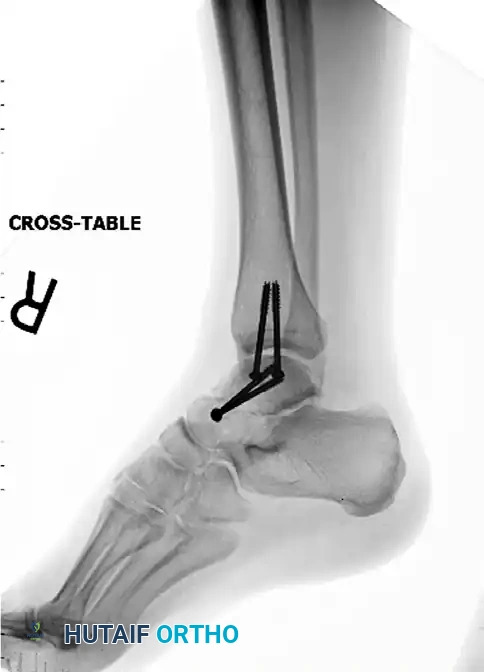

4. Hardware Fixation: Cannulated Screws

Once provisionally held with K-wires, definitive fixation is typically achieved using titanium cannulated screws (usually 3.5 mm or 4.0 mm).

* Anteroposterior (AP) screw placement is standard. One screw is placed from the medial side of the talar head into the medial body, and a second is placed from the lateral process into the lateral body.

* Screws must be countersunk to prevent impingement on the navicular or anterior tibial plafond.

Post-operative Fixation with Cannulated Screws: